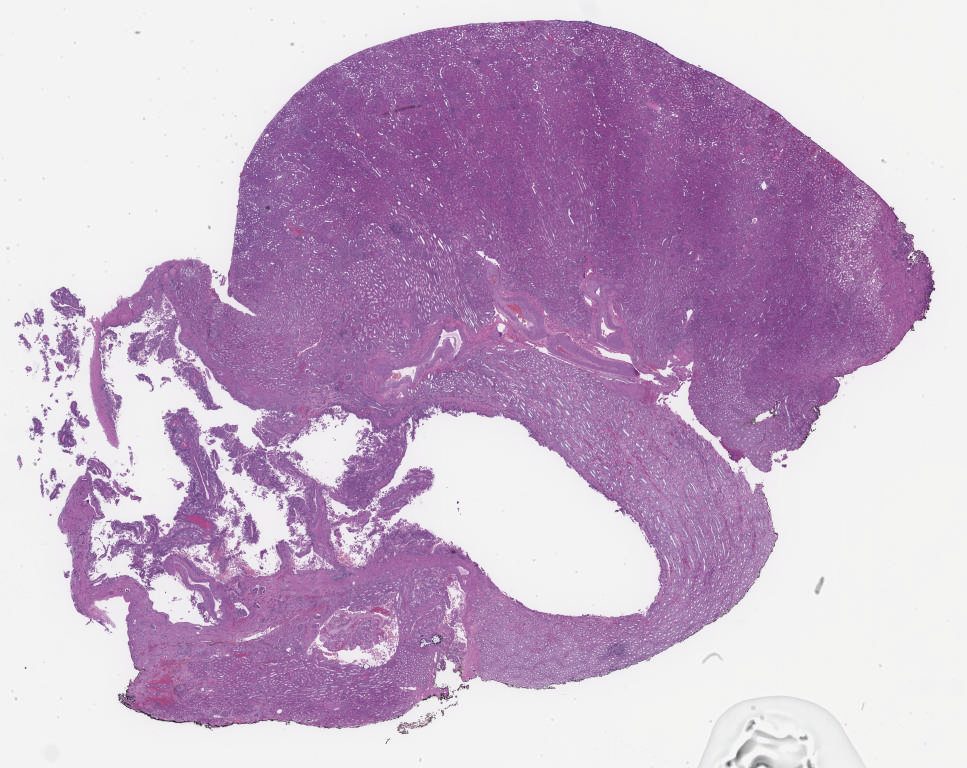

681886.svs

685867.svs